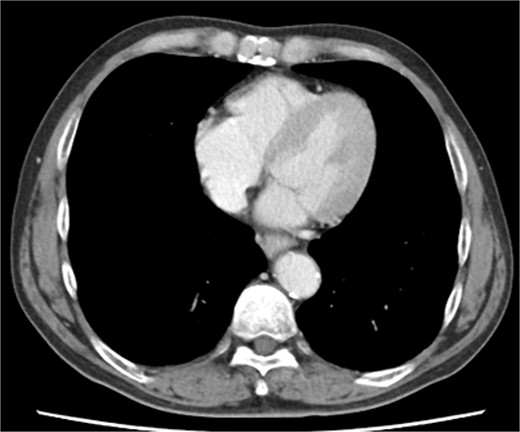

The patient underwent robotic subtotal esophagectomy, two-region lymph node dissection, narrow gastric tube was created by hand assisted laparoscopy and cervical anastomosis was performed via the retrosternal route. The operation took 613 min, with minimal blood loss. The retrosternal route under camera assist was created without bleeding, and no intraoperative hemodynamic changes or complications were observed. The pathological stage was pT1b(SM2)pN1M0 pStage II (Japanese Classification of Esophageal Cancer, 12th Edition). Esophageal fluoroscopy on postoperative day (POD) 7 showed a minor leak at the anastomotic site, which improved by POD 14 after cervical wound release and drainage. The minor leak at the anastomosis site has been the cause of prolonged hospital stay. The patient experienced sudden intermittent chest pain on POD 17, but his vital signs remained stable. Echocardiography revealed an increased amount of pericardial fluid. He was diagnosed with pericarditis and prescribed colchicine by cardiologist; however, pericardial fluid levels continued to increase. Pericardiocentesis with pericardial catheter insertion was performed on POD 34, revealing bloody pericardial fluid. Blood drainage persisted at approximately 300 ml/h. Urgent contrast-enhanced CT revealed contrast extravasation from the anterior right ventricle (Fig. 2). Coronary angiography revealed aneurysmal changes in the peripheral right ventricular branch without apparent hemorrhage (Fig. 3).

Contrast-enhanced computed tomography shows contrast extravasation in the anterior right ventricle (arrow).